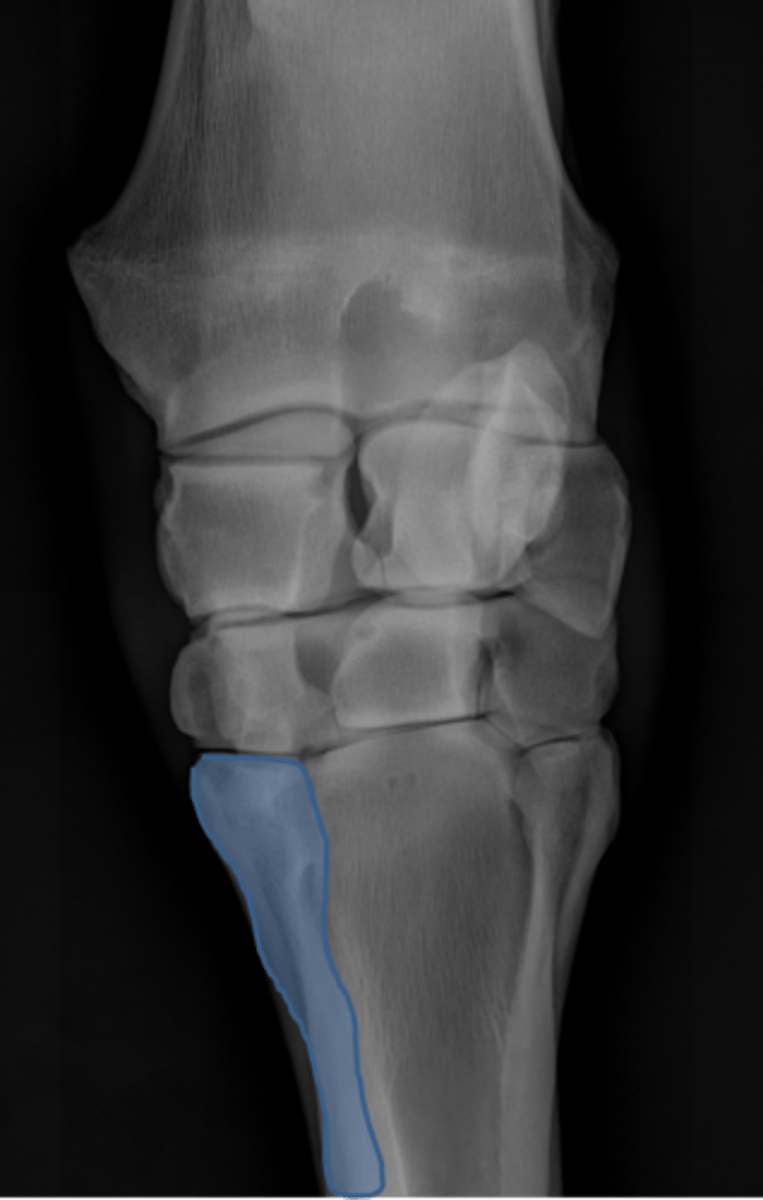

Carpus, lateral

ID joint and view

Accessory carpal bone

Second metacarpal (medial splint)

Fourth metacarpal (lateral splint)

Cannon bone